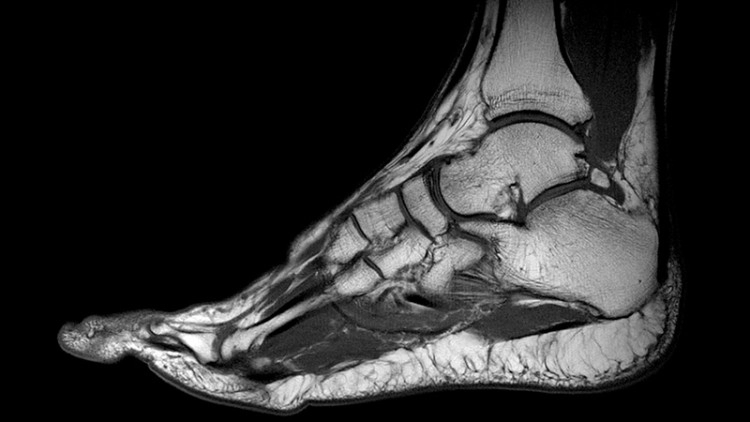

МРТ голеностопного сустава

При невозможности точно установить причину болей, выявить патологические изменения поможет МРТ голеностопного сустава. Прогрессивная методика позволяет достоверно диагностировать травмы, воспаления, опухоли и другие патологии мышечной ткани, связок, сухожилий, сосудов, нервных волокон и других тканей. Исследование часто назначают перед операцией исправления вальгусной деформации, лечения артроза или плоскостопия. Среди основных преимуществ исследования хирурги и ортопеды называют высокую информативность, безопасность и безболезненность магнитно-резонансной томографии.

Основная цель проведения исследования заключается в визуализации структур сустава, отображении травм и патологий мягких тканей. Томография позволяет выявить повреждения тканей, опухоли, очаги воспаления, застарелые гематомы, надрывы и растяжения связок, истончения и дегенеративные процессы в тканях.